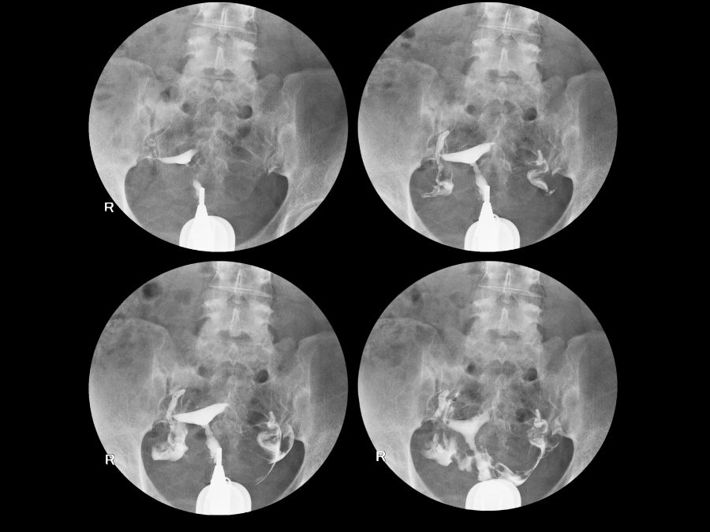

Hysterosalpingography (HSG), also known as a “dye X-ray of the uterus,” is a special type of X-ray in which a contrast dye is used to detect any blockage in the fallopian tubes, as well as to provide accurate information about the shape and size of the uterus.(1)

During the test, a contrast dye is injected through the vagina so that it appears clearly on the X-ray screen. This allows the doctor to see how the dye moves through the fallopian tubes and uterus, showing if there are any blockages or abnormalities.(1)

- X-ray images are taken as the dye spreads through the uterus and fallopian tubes.